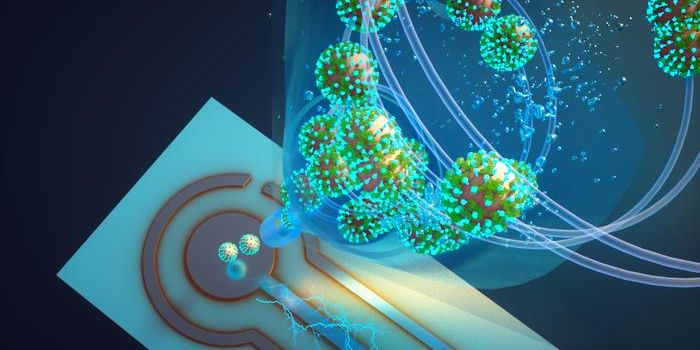

JUL 10, 2023TechnologyA recent study published in Nature Communications examines a new proof-of-concept device capable of detecting Covid-19 v ...